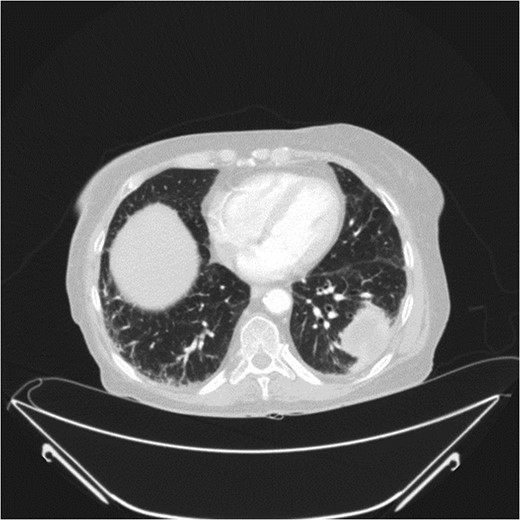

A 78-year-old female presented with worsening abdominal pain over 1 week, with onset of symptoms occurring 3 months prior. No history of recurrent fever or weight loss was elicited. There were no changes in bowel habits and she denied melena or hematochezia. She endorsed a normal colonoscopy three years prior. Of note, she was diagnosed with a biopsy proven squamous cell cancer of her left lower lobe 4 months earlier (Fig. 1). A PET scan performed just three weeks prior to her presentation demonstrated significant FDG uptake in the left lower lobe as well as the cecum, with no convincing evidence of regional nodal disease in the lungs (Figs 2 and 3).